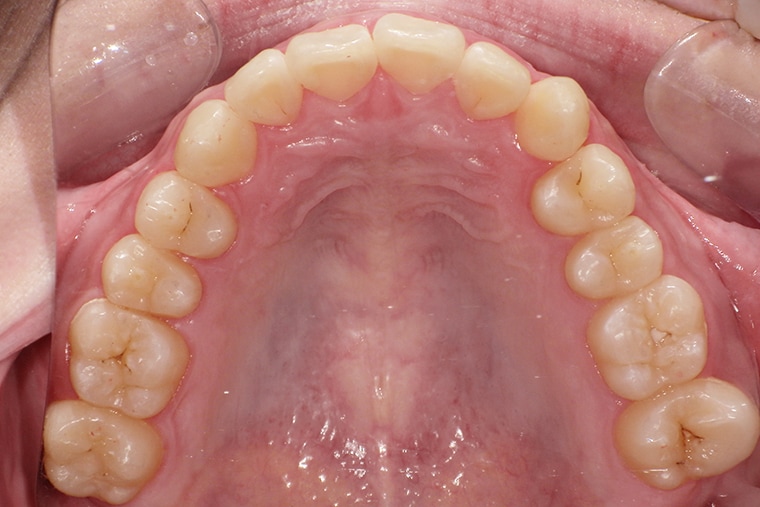

AFTER